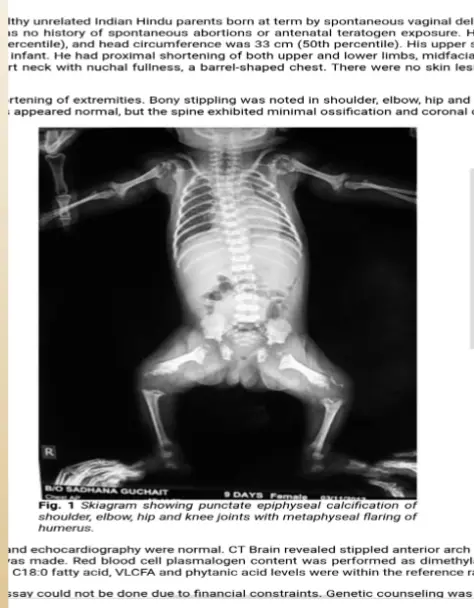

- Radiographic: Stippling of epiphyses (Chondrodysplasia punctata).

3. Other Manifestations

- Hematologic: Anemia, neutropenia, thrombocytopenia, rare aplastic anemia.

- Neurologic: Hydrocephalus, macrocephaly.